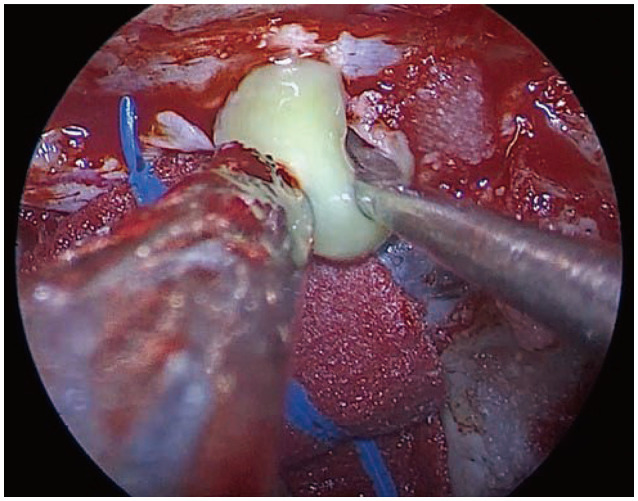

Recurrence of Rathke's cleft cysts (RCC) following surgery is not uncommon. We present a 33-year-old male patient with chronic headache and visual disturbances whose MRI showed mostly cystic, suprasellar mass with peripheral enhancement. Endoscopic extended transsphenoidal approach and tumor resection was performed and RCC was pathologically confirmed postoperatively. Early recurrence was first suspected at 3 months following surgery, and his serial MRIs showed a recurred mass without associated clinical symptoms. Upon further histopathological study, extensive squamous metaplasia and high Ki-67 were seen. Also, in this study, we discuss important factors associated with cyst recurrence following surgery.